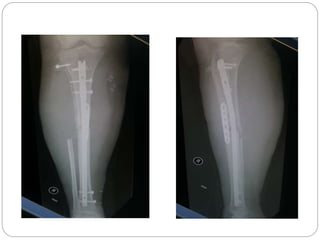

This document discusses 8 oncology cases. Case 1 involves a 40-year old female with right knee pain. Case 2 is a 28-year old male with a left subtrochantric fracture from a MVA who is now experiencing increasing left knee pain and swelling. Biopsy results showed high-grade osteosarcoma. Case 3 is a 30-year old female with breast cancer and bone metastases causing bilateral hip pain.